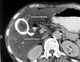

Calculus eroding through bladder wall